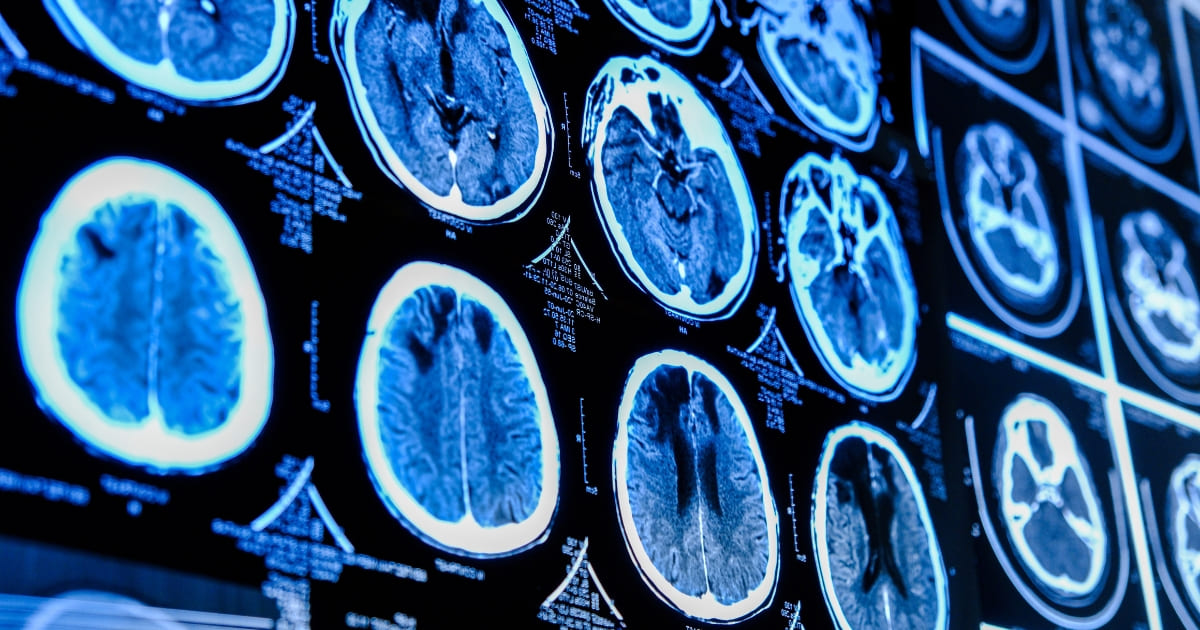

มะเร็งระบบประสาทและสมองมีต้นเหตุมาจากเซลล์สมองหรือไขสันหลังแบ่งตัวผิดปกติจนกลายเป็นเนื้องอก ซึ่งมีทั้งเนื้องอกที่ไม่ใช่เนื้อร้ายและเนื้องอกที่เป็นเนื้อร้าย ส่งผลกระทบรุนแรงต่อระบบประสาท ทำลายสมองและไขสันหลัง อาจร้ายแรงถึงชีวิต จึงต้องได้รับการรักษาโดยเร็วที่สุดโดยแพทย์เฉพาะทางที่มีความชำนาญและเทคโนโลยีการรักษาที่ทันสมัยเพื่อลดความรุนแรงและเพิ่มโอกาสในการกลับมาใช้ชีวิตได้อย่างมีคุณภาพอีกครั้ง

บริการโรคมะเร็งระบบประสาทและสมอง (Neuro – Oncology) ศูนย์สมองและระบบประสาท โรงพยาบาลกรุงเทพอินเตอร์เนชั่นแนล พร้อมตรวจวินิจฉัยมะเร็งระบบประสาทและสมองด้วยการตรวจคอมพิวเตอร์สมอง (CT Scan)  ตรวจสมองด้วยคลื่นสนามแม่เหล็ก (MRI) และวางแผนการรักษาที่ช่วยลดความรุนแรงของโรค ไม่ว่าจะเป็นการผ่าตัดแบบแผลเล็ก Minimally Invasive Surgery การฉายรังสีกำจัดเซลล์มะเร็งที่เหลือหรือไม่สามารถผ่าตัดได้ การให้ยาเคมีบำบัดหรือยามุ่งเป้า โดยอาจใช้หลายวิธีร่วมกันเพื่อให้ผู้ป่วยกลับมาใช้ชีวิตได้อย่างมีคุณภาพ ภายใต้การดูแลของทีมแพทย์เฉพาะทางและทีมสหสาขาที่มีความชำนาญและเทคโนโลยีที่ทันสมัย ตอบโจทย์การดูแลรักษาผู้ป่วยเฉพาะบุคคล